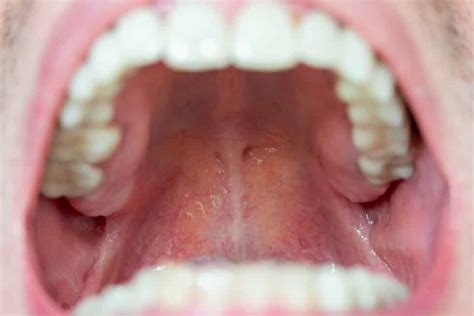

Inflamación del Paladar

El paladar es el techo de la boca, el cual separa la cavidad oral de la cavidad nasal. De vez en cuando el paladar puede inflamarse, lo cual puede deberse a varias causas potenciales, la mayoría de las cuales se subsanan con tratamientos mínimos.

Al fondo del paladar, conocido como la parte blanda, podemos encontrar la úvula, conocida de manera coloquial como campanilla. Algunas de las causas más comunes en la inflamación de este músculo es la sequedad bucal o una infección.